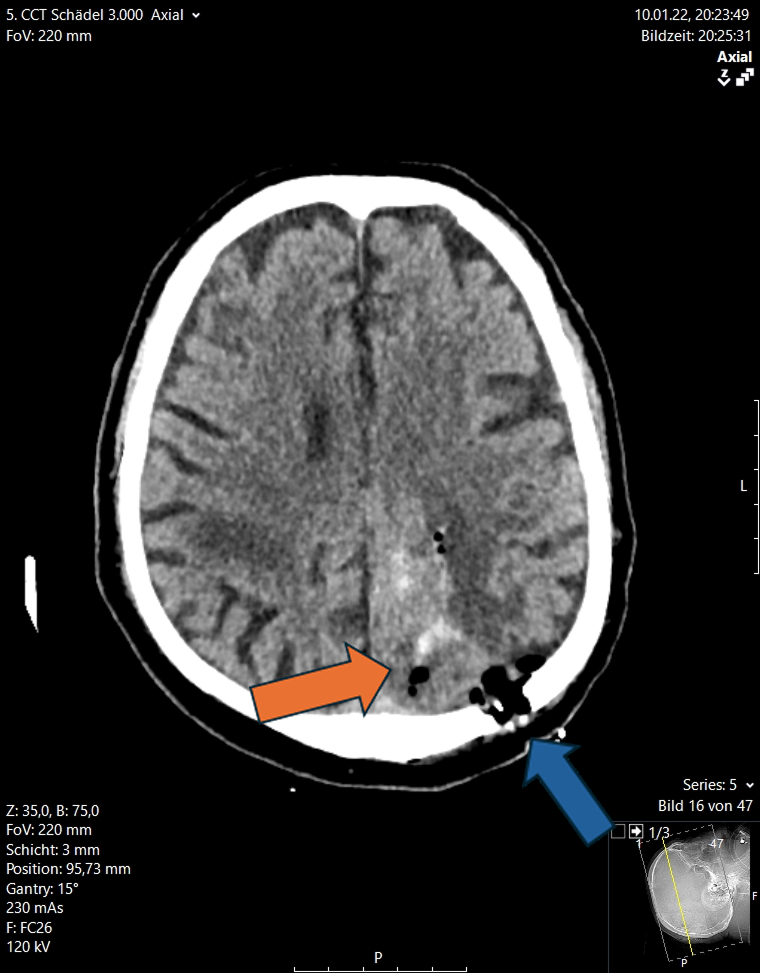

Περισσότερες λεπτομέρειες για τις ενδοεγκεφαλικές αιμορραγίες μπορείτε να διαβάσετε στο αντίστοιχο ενότητα στις παθήσεις (ενδοεγκεφαλικές αιμορραγίες)

Εδώ θέλουμε να τονίσουμε ότι σήμερα είναι δυνατό να αφαιρεθεί μια τέτοια αιμορραγία μόνο μέσω ενός ελάχιστα επεμβατικού ενδοσκοπικού χειρουργείου διάρκειας 20 με 30 λεπτών αντί για τα παραδοσιακά χειρουργεία στα οποία γινόταν μεγάλες κρανιοτομές. Στις εικόνες 12 και 13 απεικονίζονται οι προεγχειρητικές και μετεγχειρητικές εικόνες από δύο ασθενείς με ενδοεγκεφαλική αιμορραγία. Αυτές αφαιρέθηκαν ενδοσκοπικά μέσω μιας απλής κρανιοανάρτησης (1 εκ.)